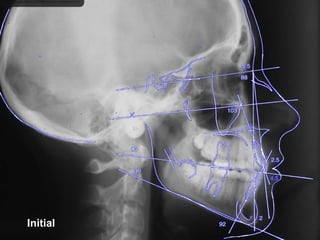

Treatment Planning โ€ข Ceph numbers โ€ข Model analysis โ€ข Pano X-rays โ€ข Facial analysis โ€ข Impact of growth/aging โ€ข Vestibular bone density โ€ข Tongue position/airway โ€ข How light a wire do I need to stimulate blood flow?

Initial 16 yearsโ€“ 5 months Class II, severe crowding, bilateral posterior crossbite